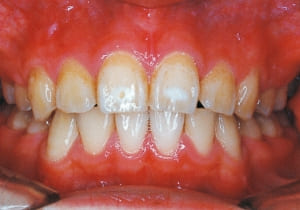

26 After Retention 7-8-’96

The facial type changed from backward divergent to straight between the initial visit and after retention (27–31). Cephalometric X-rays reveal significant mandibular growth (32).

Treatment period from initiation to completion of active treatment lasted 6 years and 2 months, with appliances worn for 3 years and 8 months of that time. Retention lasted 2 years and 2 months following active treatment.